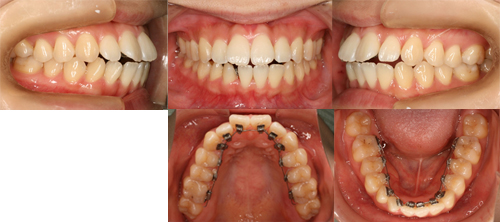

上の前歯に装置を装着して約1ヶ月。主訴だった前歯のデコボコがだいぶ並んできました。

上下ともに順調に改善してきてると思います。